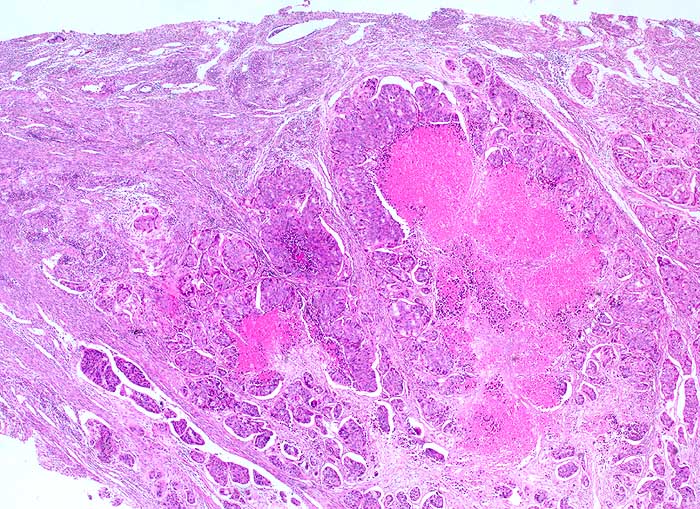

pit/ Zervixmetastase eines Kolonkarzinoms

Zervixmetastase eines Kolonkarzinoms

maligner Tumor

Zervix

Eine für die Lokalisation atypische Morphologie eines Tumors sollte immer an die Möglichkeit einer Metastase denken lassen. Im Zweifelsfall lohnen sich eine Rückfrage beim Kliniker und das Studium aller Vorbefunde.